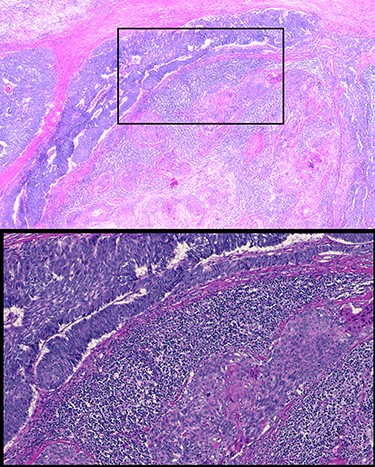

Sixty-three-year-old male was with the history of diabetes and hypertension who presented with 2 days of new onset, intermittent and non-pleuritic left-sided chest pain, with a few months of new onset exertional dyspnea. Chest X-ray showed a convex shaped mass at the left hilum. Chest CT angiography revealed a 5.6 × 7.1 × 5.4 cm hypodense mass in the anterior mediastinum involving the adjacent anterior medial left upper lobe, and adjacent mildly enlarged aorticopulmonary window lymph nodes (Fig. 1). PET scan demonstrated a hypermetabolic anterior mediastinal mass adjacent to medial left upper lobe highly suggestive of malignancy (Fig. 2). Ultrasound-guided core needle biopsy showed nests of small cells with peripheral palisading and focal abrupt transition to squamous cell, consistent with basaloid carcinoma of thymic gland. Immunostainings of the tumor cells were positive for cytokeratin AE1/AE3, cytokeratin CK904, p63 and p40.

Chest CT angiography revealed a 5.6 × 7.1 × 5.4 cm hypodense mass in the anterior mediastinum involving the adjacent anterior medial left upper lobe.